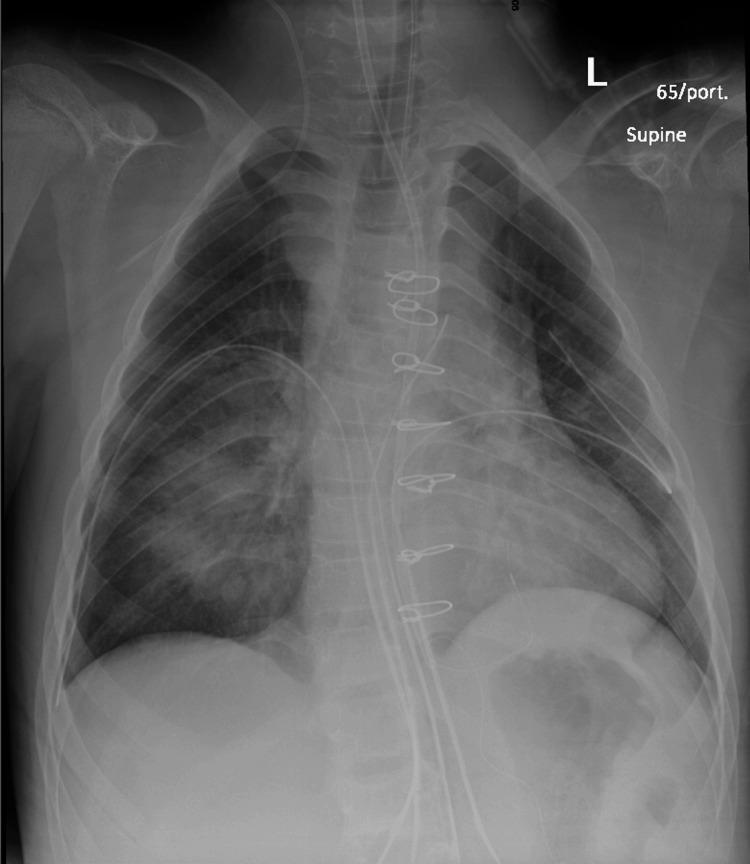

Baraitser-Winter syndrome (BRWS) is a rare genetic disorder caused by mutations in the ACTB and ACTG1 genes. It is characterized by intellectual disability, physical malformations, and dysmorphic craniofacial features. Additionally, cardiovascular abnormalities may also be present. We present a case of a 15-year-old boy with BRWS associated with congenital bicuspid aortic valve and severe aortic insufficiency which was managed successfully with Ross procedure.

巴拉伊泽-温特综合征(BRWS)是一种由ACTB和ACTG1基因突变引起的罕见遗传性疾病。其特征为智力残疾、身体畸形以及颅面部畸形特征。此外,也可能存在心血管异常。我们报告一例15岁患有BRWS并伴有先天性二叶式主动脉瓣和严重主动脉瓣关闭不全的男孩病例,该病例通过罗斯手术成功得到治疗。